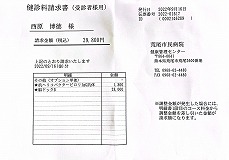

0140 健康診断結果

0109 24.7.29健康診断=pdf

0108 ①22.8.23荒尾市民病院=pdf ②2023-08-21健康診断結果.pdf 8/10(木)受診 荒尾市民病院

①

②

②